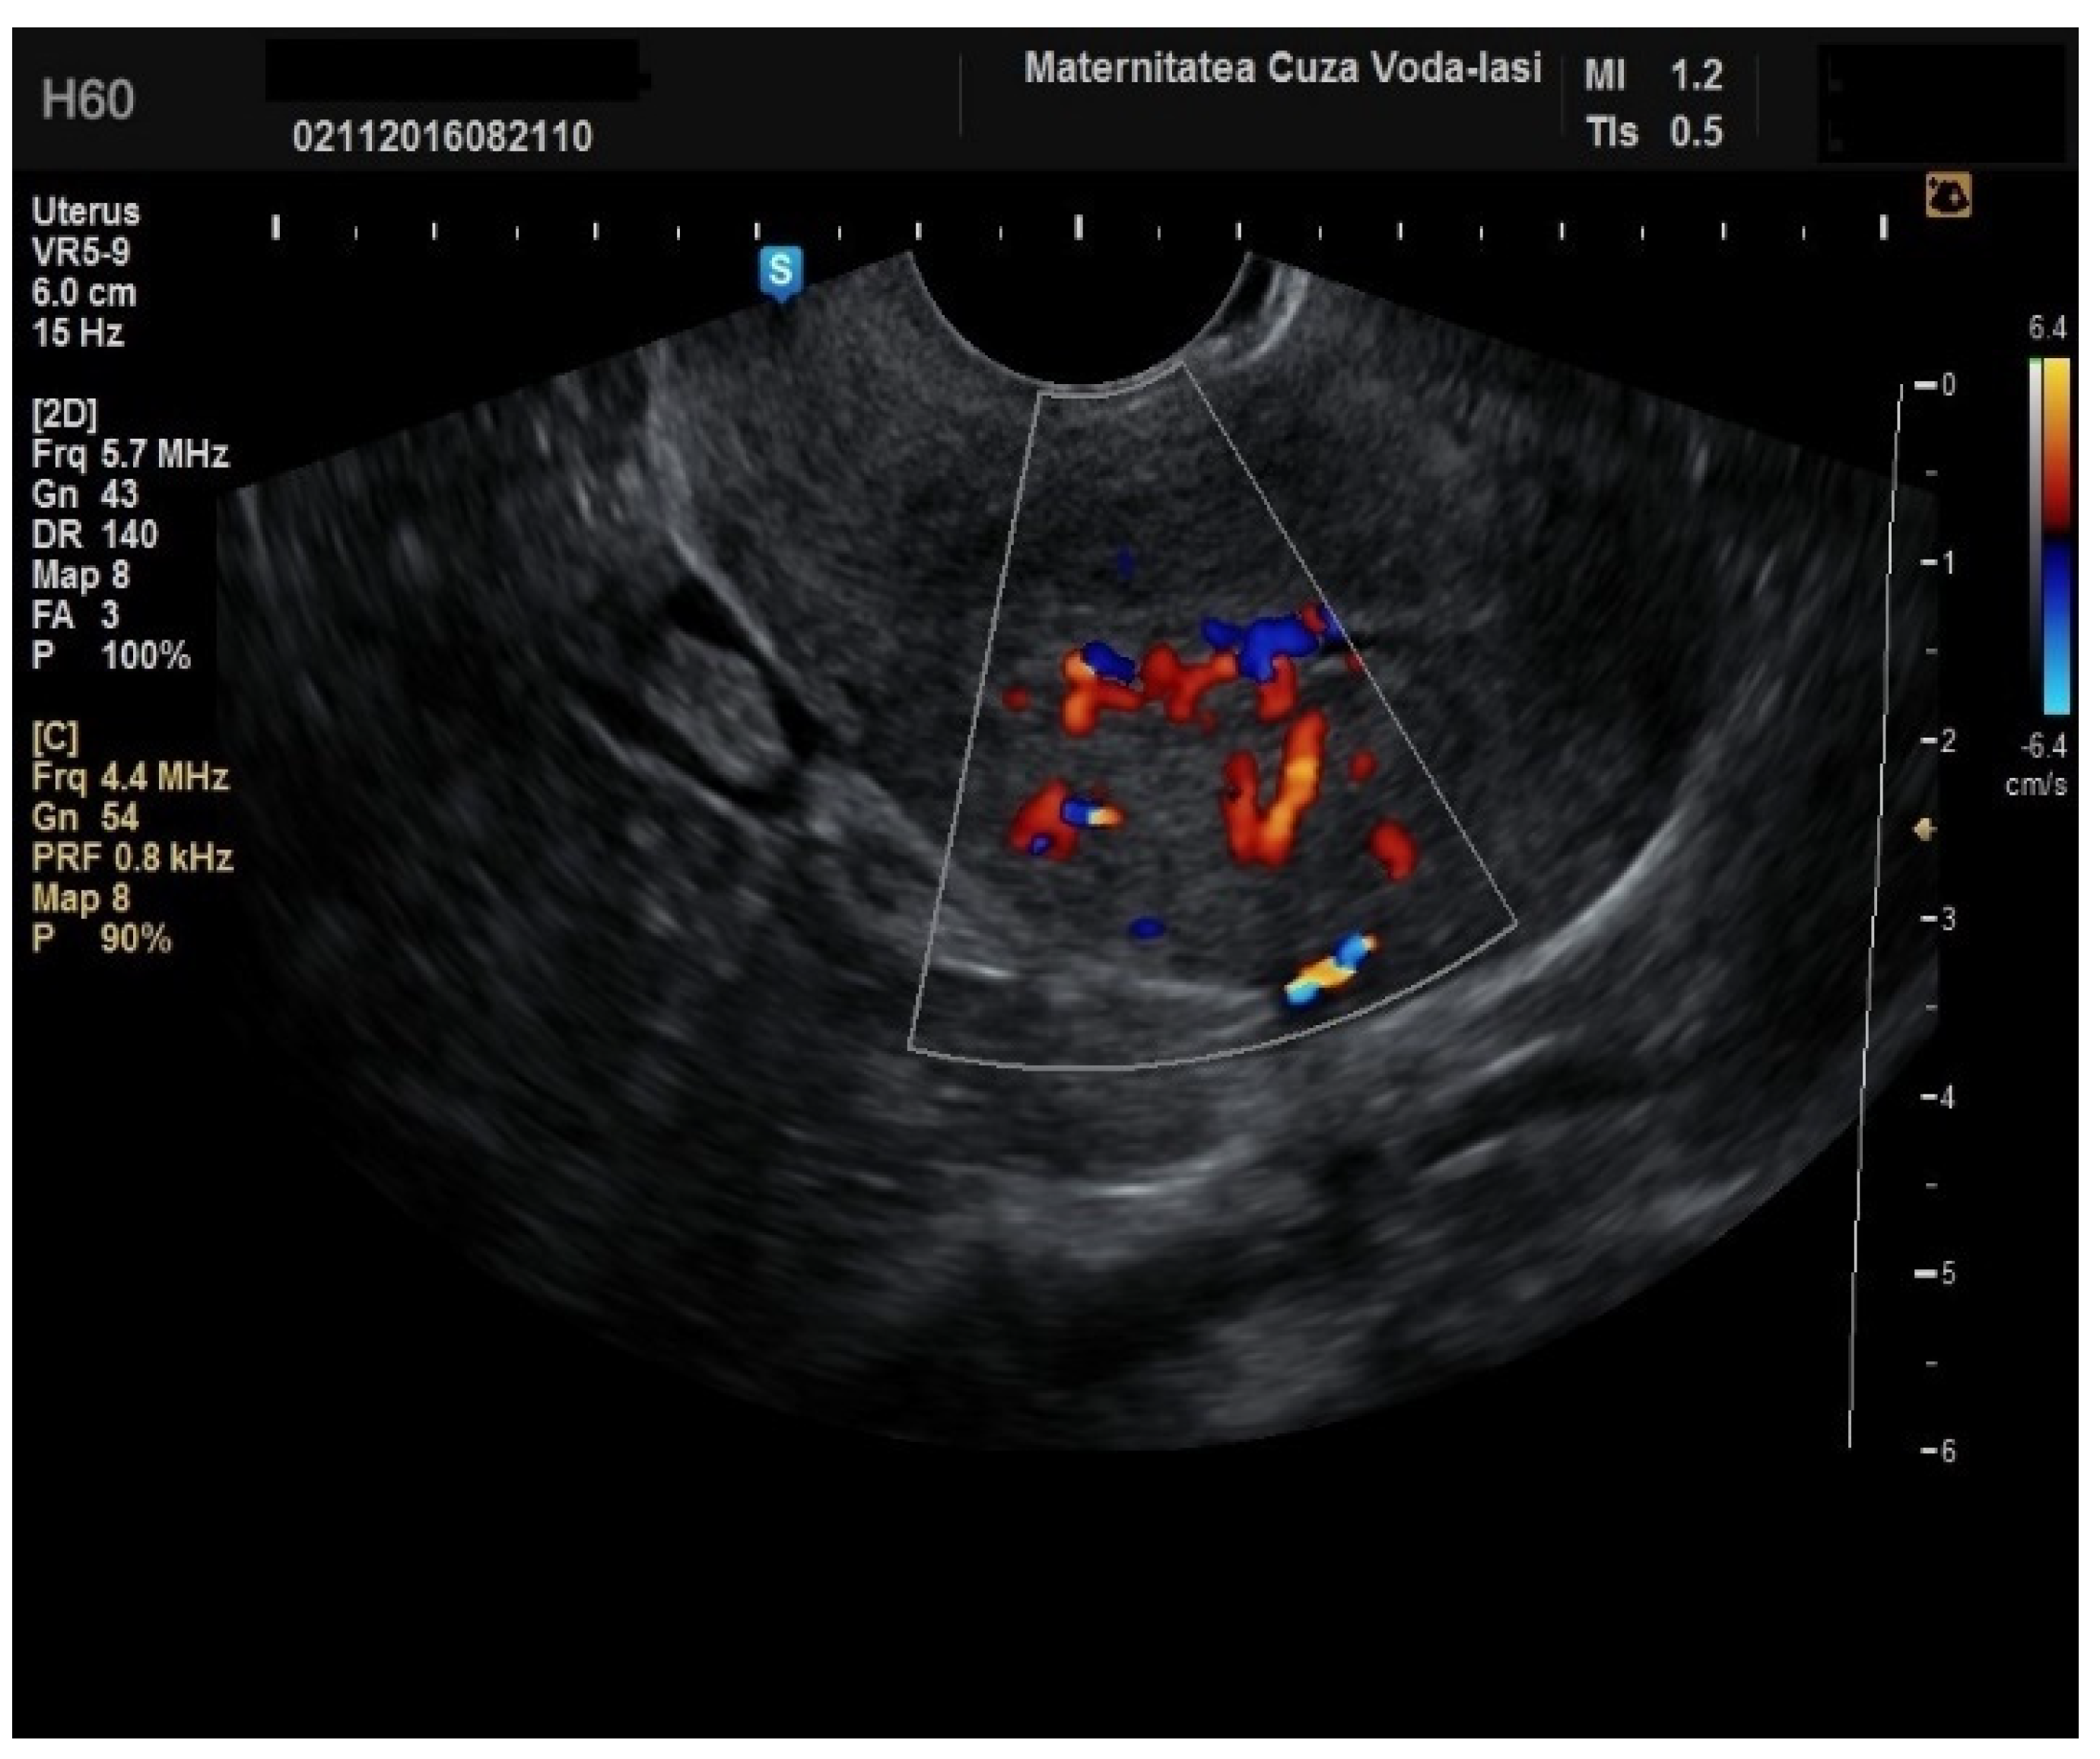

Regarding the color Doppler assessment, a vascular score of 1 usually excludes endometrial cancer, with a sensitivity of 87.5% and a specificity of 79% (Figure 8). This is due to the presence of a high number of newly formed vessels in malignant tumors (Figure 9).

Furthermore, color Doppler imaging proved valuable in more accurately determining myometrial invasion. The predominant feature of blood vessels in endometrial cancer was the presence of scattered vessels (Figure 10), which demonstrated a sensitivity of 50% (95% CI: 0.2152 to 0.7848) and a specificity of 94.74% (95% CI: 0.8563 to 0.9819). Additional vascular aspects indicative of endometrial cancer were the presence of vessels with various branches (Figure 11) and color splashes (Figure 12).

Figure 9. Color Doppler vascular score 4 in endometrial cancer.

Figure 10. Color Doppler imaging for assessing endometrial invasion in endometrial cancer: scattered vascular patterns.